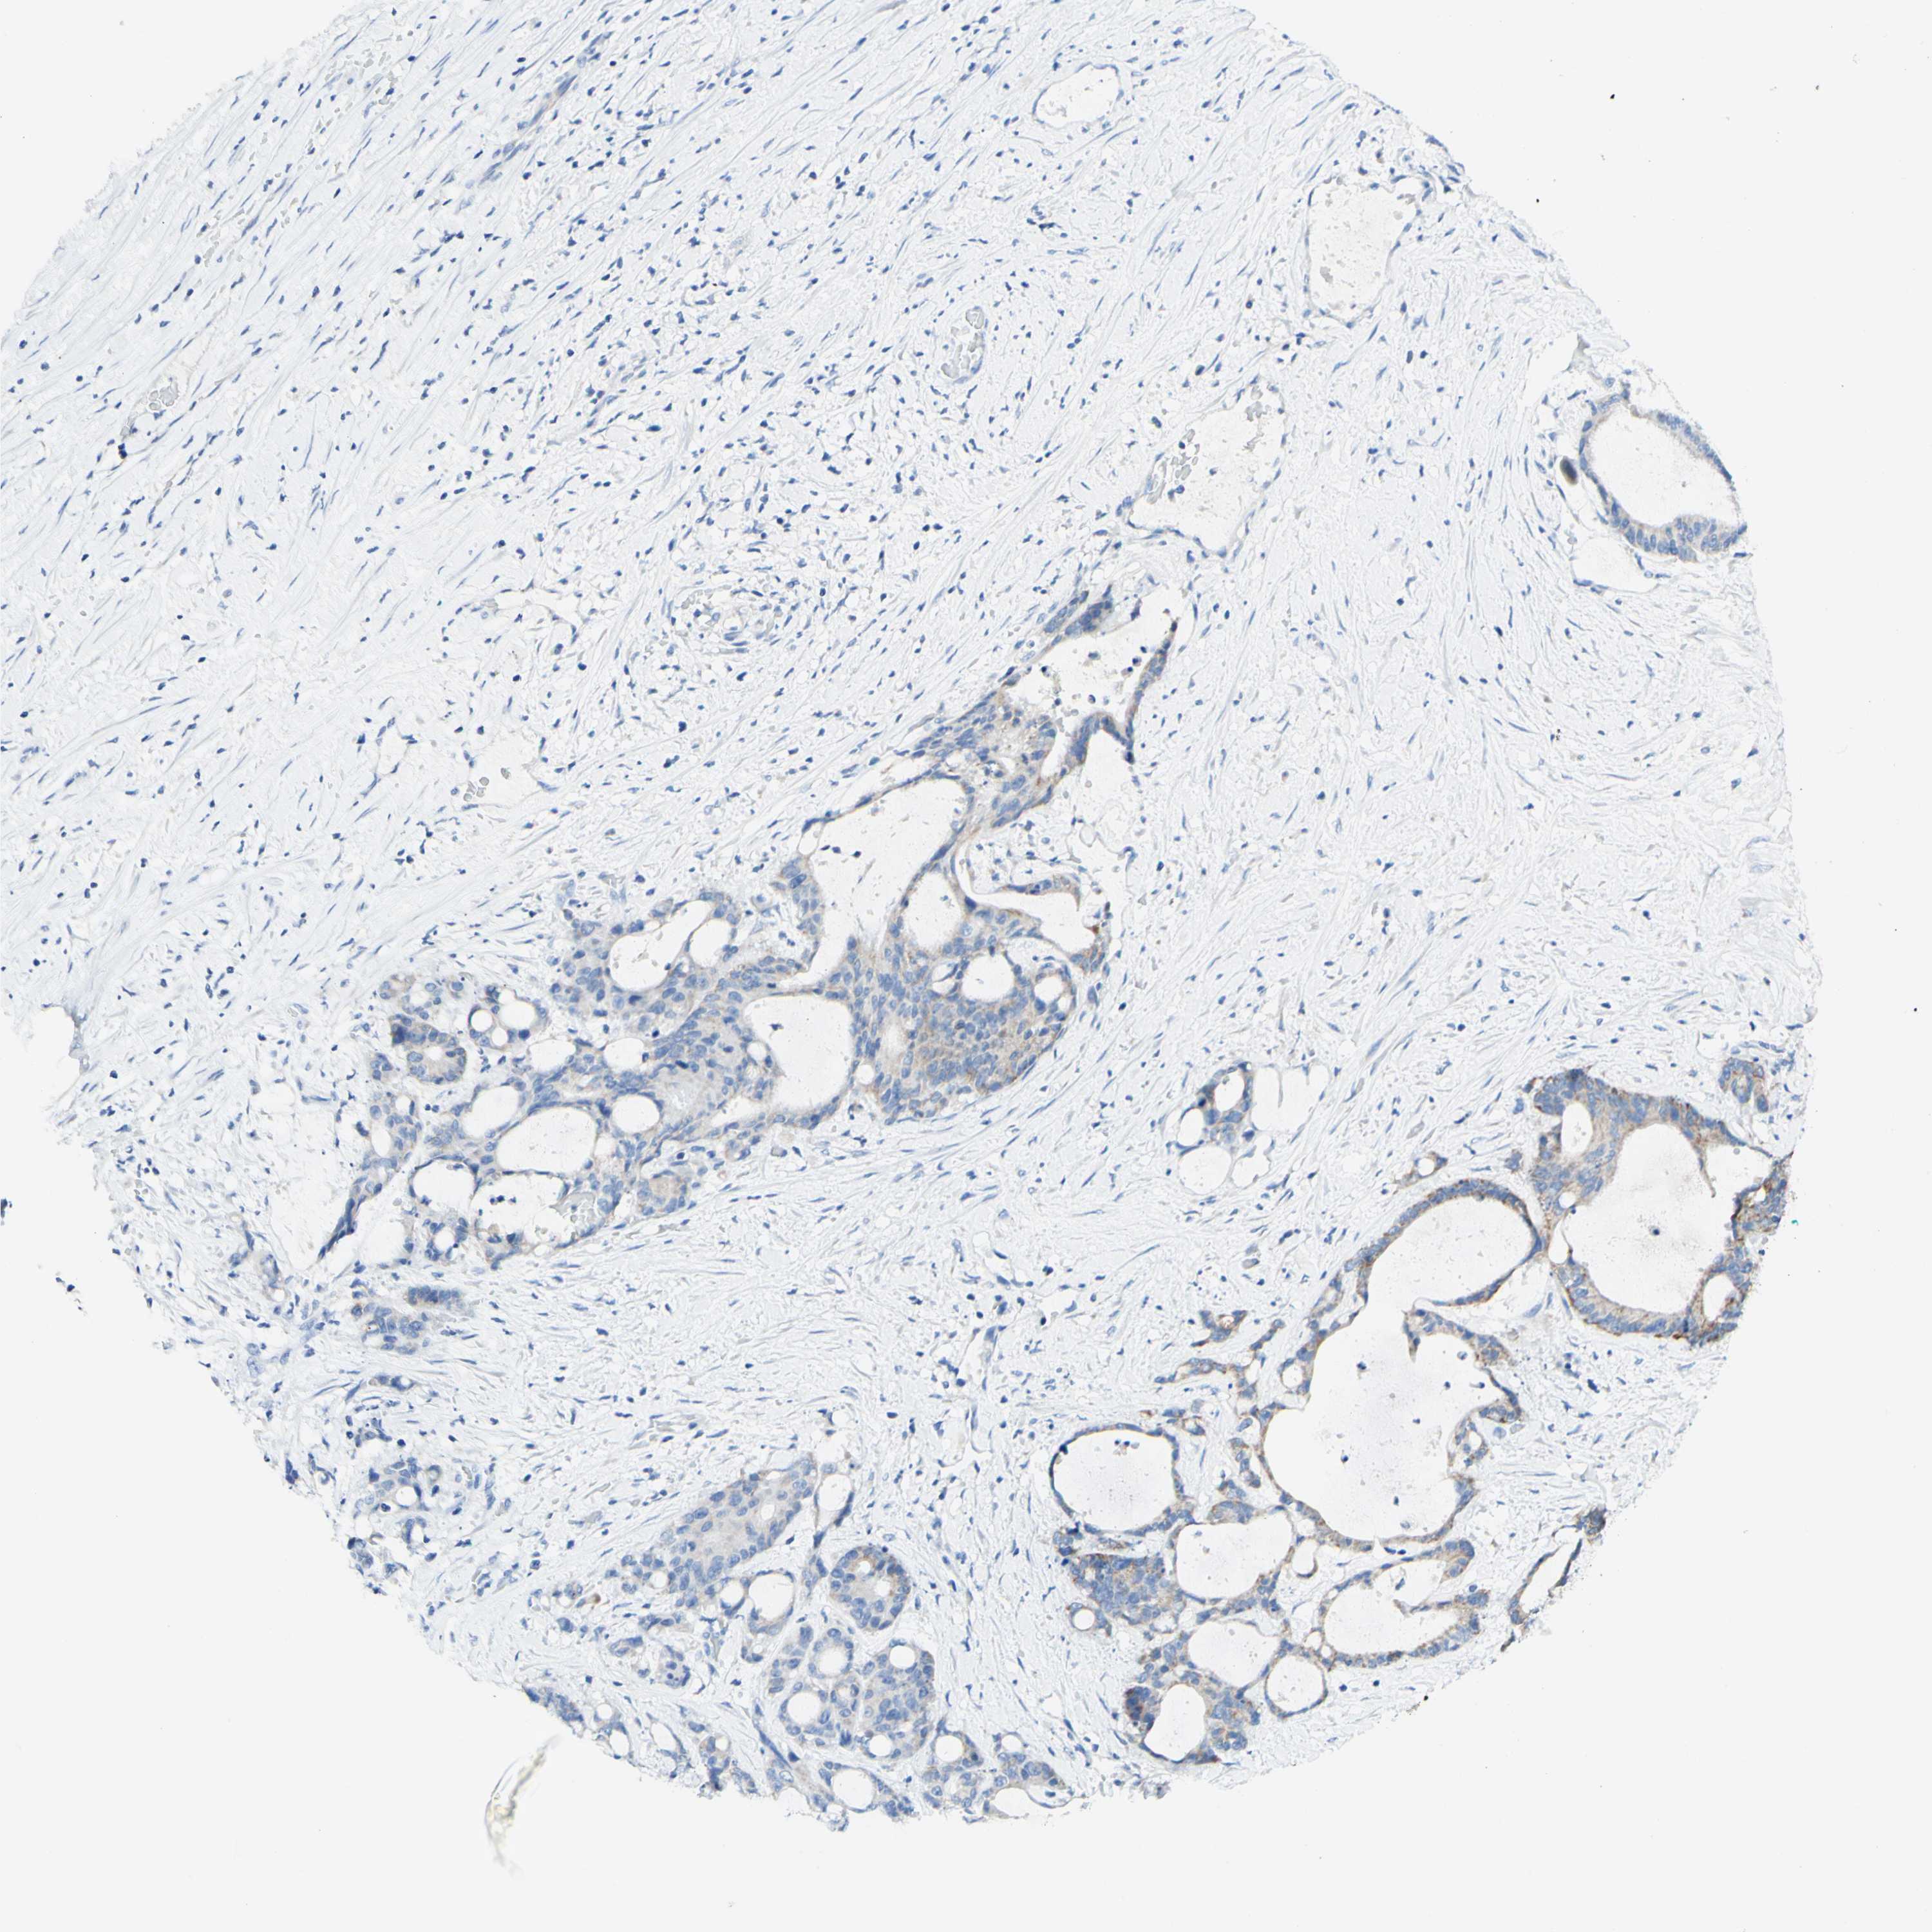

LIVER CANCER - Protein expressioni

A mouse-over function shows sample information and annotation data. Click on an image to view it in a full screen mode. Samples can be filtered based on level of antibody staining by selecting one or several of the following categories: high, medium, low and not detected. The assay and annotation is described here.

Note that samples used for immunohistochemistry by the Human Protein Atlas do not correspond to samples in the TCGA dataset.

Antibody stainingi

Antibody staining in the annotated cell types in the current human tissue is reported as not detected, low, medium, or high, based on conventional immunohistochemistry profiling in selected tissues. This score is based on the combination of the staining intensity and fraction of stained cells.

Each image is clickable and will lead to virtual microscopy that enables deeper exploration of all samples and also displays staining intensity scores, fraction scores and subcellular localization as well as patient and tissue information for each sample.

Antibody HPA011036

Antibody HPA011057

Staining

High

Medium

Low

Not detected

Intensity

Strong

Moderate

Weak

Negative

Quantity

>75%

75%-25%

<25%

None

Location

Nuclear

Cytoplasmic/membranous

Cytoplasmic/membranous,nuclear

Cholangiocarcinoma

Carcinoma, Hepatocellular, NOS